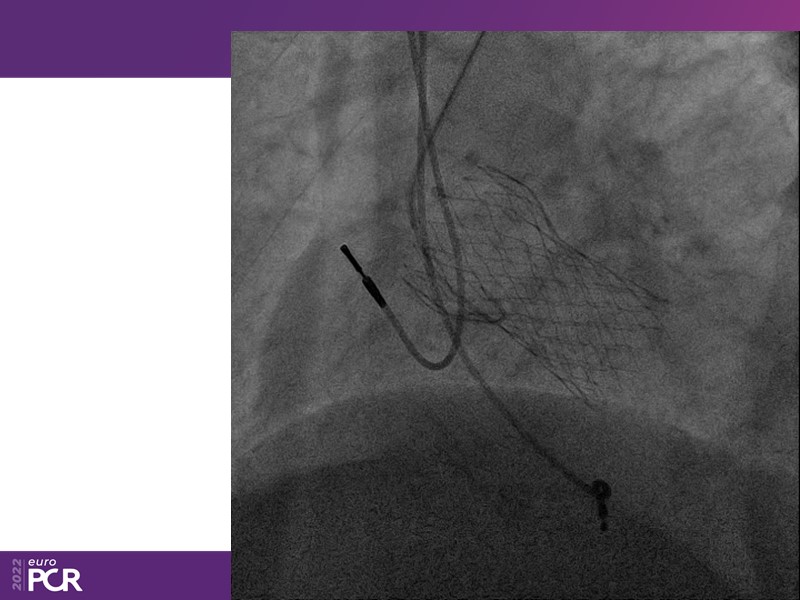

Consult this session to learn how to contribute to streamlined pre- and post-TAVI patient pathways, to discover updates on the optimised TAVI procedure and appreciate the variances in different valve designs and the long-term patient outcomes, as well as to discuss the right time of PCI in TAVI patients (steps on the procedure).

- To discuss the right time of PCI in TAVI patients (steps on the procedure)